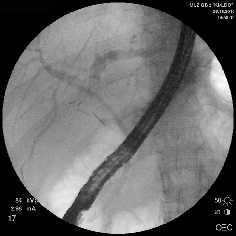

Rg-фото. Бужирование стриктуры холедоха

Rg-фото. Баллонная дилятация стриктуры холедоха

Rg-фото. Стентирование холедоха

Рис. 2. Наиболее часто выполняемые эндоскопические вмешательства

Ятрогенные повреждения холедоха с рубцовой стриктурой были выявлены у 15 больных. Эндоскопические методы диагностики и лечения в виде РХПГ, бужирования и стентирования обладают высокой эффективностью. У ряда больных эндоскопические манипуляции ограничились диагностическими вмешательствами с последующей хирургической коррекцией.

Рубцовая стриктура средней трети холедоха + холедохолитиаз

Рубцовая стриктура верхней трети холедоха

Рис. 7. РХПГ при рубцовой стриктуре холедоха